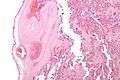

| Intermediate magnification micrograph of the placental disc showing a thrombosed fetal vein, as may be seen in fetal thrombotic vasculopathy. H&E stain. | |

Fetal thrombotic vasculopathy is a chronic disorder characterized by thrombosis in the fetus leading to vascular obliteration and hypoperfusion.

It can be diagnosed by histomorphologic examination of the placenta and is characterized by fetal vessel thrombosis and clustered fibrotic chorionic villi without blood vessels.